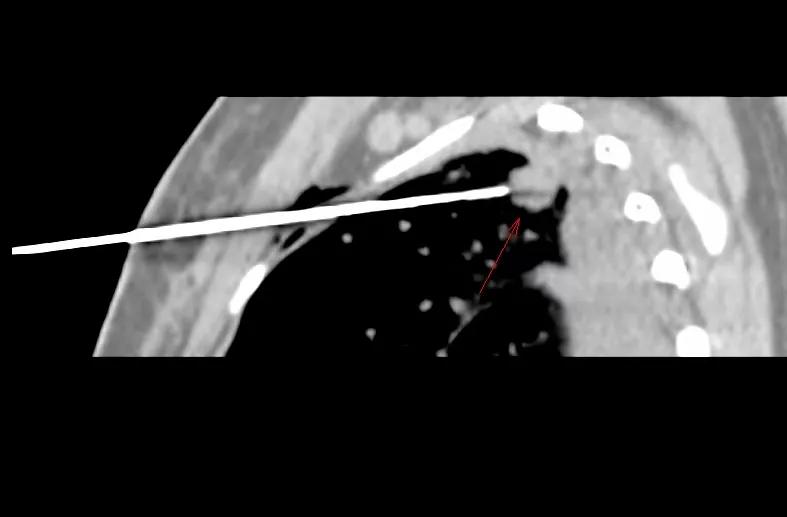

穿中结节,到边缘即可,这样可取材整个结节穿刺方向上的组织。

矢状位重建图像,穿刺深度较深,10cm。